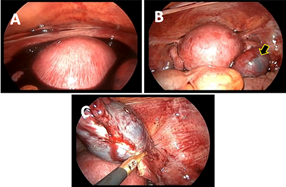

Prior to surgery, the patient was placed on an intramuscular progesterone injection combined with an antispasmodic infusion (phloroglucinol in glucose serum). The aim of treatment was to perform a salpingectomy while preserving the intrauterine twin pregnancy. Laparoscopic surgery was opted for, which revealed the following findings: a moderate hemoperitoneum with multiple blood clots, an enlarged gravid uterus, a ruptured right ampullary pregnancy no longer actively bleeding and normal left adnexa (Figure 2).

300 ml of hemoperitoneum were aspirated first and thereafter a total right salpingectomy was performed using bipolar shears with coagulation and cutting mode. An ultrasound performed immediately post- operatively showed an evolving intrauterine twin pregnancy, and the patient continued with her treatment consisting of progesterone twice a day 200 mg intravaginally and phloroglucinol three times 80 mg intrarectally. Another ultrasound scan performed a week after the operation showed the death of an intrauterine twin at nine weeks. Closer prenatal visits than the usual schedule were performed. At 38 weeks, the patient underwent an elective caesarean section which resulted in the extraction of a female healthy new-born weighing 2500 g with an APGAR of 9/9/10, a length of 48 cm, a head circumference of 33 cm and a chest circumference of 32 cm (Figure 3). Examination of the placenta revealed a single placenta with a para-central umbilical cord insertion without anomaly, suggesting the disappearance of the dead twin at nine weeks.

Figure 2: A shows the hemato-peritoneum; B shows the pregnant uterus and the ruptured tubal pregnancy; C shows the salpingectomy